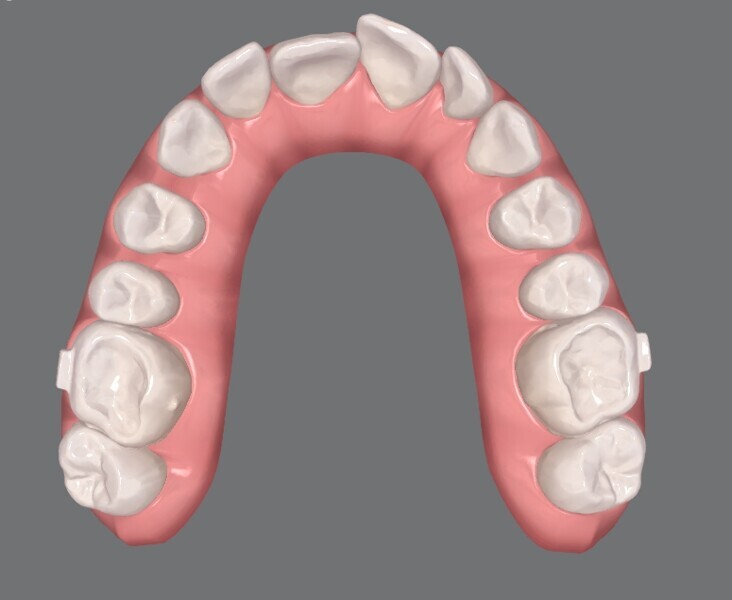

Figs. 7a–c: ClinCheck progression of the patient, showing the planned semi-sequential distalisation of the posterior teeth and overcorrection of the overbite.

Since a one-phase treatment approach was planned, an additional scan was taken immediately afterwards to produce the aligners (Invisalign, Align Technology). The goal was to achieve simultaneous bilateral molar distalisation and alignment of all the teeth using the aligners. To facilitate this, a distalisation rate of 0.2 mm per week was set, corresponding to a quarter turn of a screw with a thread pitch of 0.8 mm. The distalisation was planned asymmetrically because the molars in the maxillary right quadrant had drifted further mesially than those in the maxillary left quadrant (Fig. 6). The patient was given specific instructions on which aligner to activate the distaliser screws with. The distalisation was completed by the 20th aligner.

Additionally, semi-sequential distalisation of the premolars and canines was planned (Fig. 7). During semisequential distalisation, small gaps are initially created between the premolars to allow the aligner to better grip and move these teeth. After molar distalisation had been completed, the distaliser was kept in place to anchor the molars until the premolars had been fully distalised, preventing unwanted mesial drift. It is important to note that teeth #16 and 26, which were connected to the distaliser, could only undergo bodily distalisation. The rigid anchorage does not permit tipping and rotational movements of the first molars. Therefore, such movements of the first molars should be avoided in the ClinCheck planning. The aligner shells on teeth #16 and 26 were additionally equipped with horizontal attachments.